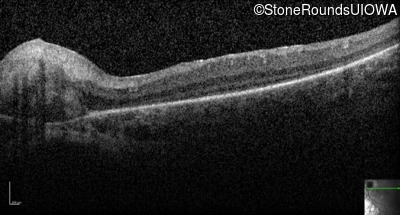

Optical Coherence Tomography - Left -

No Light Perception

Exemplar

Expanded OCT Stack

×